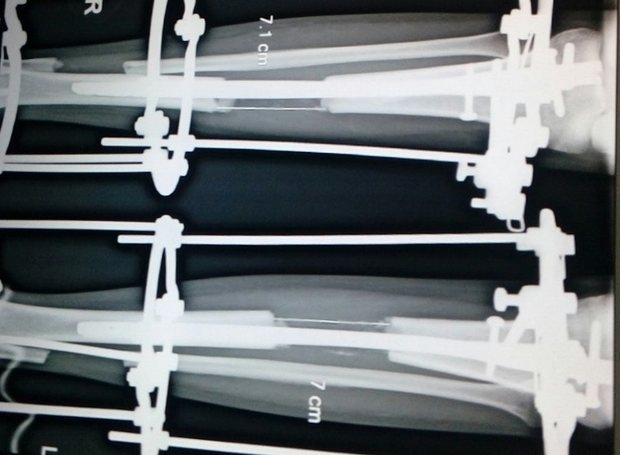

Hình chụp xương mô tả quá trình phẫu thuật kéo dài chân. |

Quy trình giúp tăng chiều cao của cô rất phức tạp và trải qua nhiều đau đớn với việc đập vỡ xương đầu gối và phải mang nẹp chân rất lâu cho tới khi có thể đi lại.